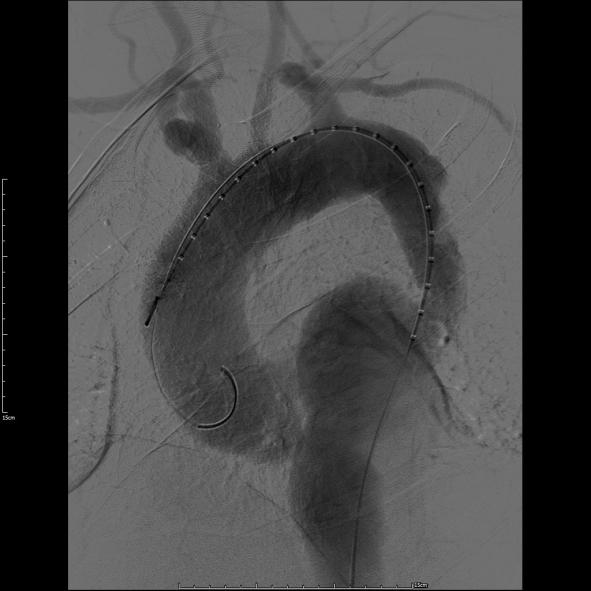

第一例患者确诊为“胸主动脉夹层合并夹层动脉瘤”,病变范围广泛。手术团队创新应用定制化打孔支架技术,术中精准定位并选择性保留重要侧支循环。该技术不仅彻底隔绝了主动脉扩张病变,更通过支架微孔有效维持了截瘫好发区域(T8-L1节段对应脊髓根动脉)的脊髓血供,显著降低了长段覆膜支架覆盖所引发的脊髓缺血及截瘫风险,为弥漫性主动脉疾病治疗提供了更安全有效的解决方案。

第一例患者术中造影